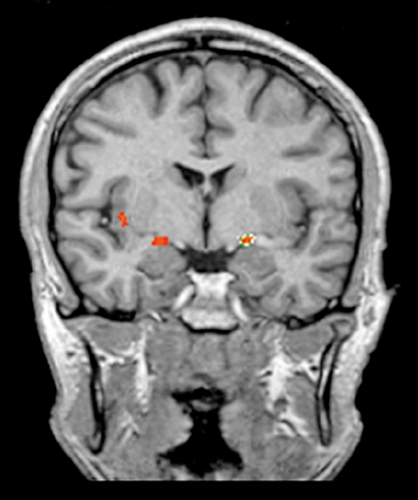

Med fMRI får man ett indirekt mått på hjärnaktivitet (Fakta). Studier som använt denna metod har visat avvikelser i hjärnaktiveringsmönster i samband med olika semantiska uppgifter hos kriminella psykopater. Individer med psykopati tog längre tid på sig att lösa semantiska uppgifter med abstrakta och konkreta ord än kontroller [56]. En del studier har undersökt friska individer som skattats högt på Psychopathy personality inventory (PPI), en checklista som kan användas för att bedöma psykopatiska drag i normalpopulationen [65].

I en annan studie jämfördes kriminella psykopater dels med kriminella icke-psykopater, dels med friska icke-kriminella, vid utförande av ett emotionellt minnestest. Resultaten visade att balansen mellan det limbiska systemet och den mer överordnade frontala delen av hjärnan tycktes vara avvikande hos de kriminella psykopaterna. Vid emotionella stimuli aktiverades hos psykopaterna områden som annars mest används för bearbetning av kognitiva uppgifter, vilket skulle kunna tala för en förändrad funktion i deras limbiska system [55].

En annan studie visade dock på överaktivering i amygdala och andra limbiska strukturer hos en grupp psykopater då de tittade på emotionella bilder [58]. Resultat från ytterligare en studie visade på skillnader mellan kriminella psykopater, skattade med PCL-R [8, 9], och kontroller med avseende på förmåga att bearbeta emotionella ansiktsuttryck. Psykopaterna uppvisade signifikant lägre aktivering i gyrus fusiformis och extrastriatala kortex när de exponerades för glada, neutrala och rädda ansikten i jämförelse med kontrollerna [52].

De studier som undersökt den neurobiologiska basen för klassisk betingning hos psykopater, där man associerar ett neutralt stimulus med ett obehagligt, har varit motsägelsefulla. En studie visade att en grupp psykopater hade kraftigare aktivering i amygdala och prefrontala kortex än kontroller, vilket tolkades som att det krävdes större ansträngning och att det tog längre tid för psykopaterna att forma associationen [60]. I ytterligare två andra studier fann man däremot att en grupp psykopater inte uppvisade samma grad av aktivering i den limbiska prefrontala banan, involverande orbitofrontala kortex, insula, anteriora gyrus cinguli och amygdala, som kontrollerna gjorde [14, 61].

Kumari och medarbetare undersökte hjärnaktivitet relaterad till arbetsminne hos en grupp individer med antisocial personlighetsstörning, en grupp schizofrena individer och en grupp friska kontroller. Jämfört med den friska kontrollgruppen visade individer med antisocial personlighetsstörning lägre aktivitet i vänster frontallob och anteriora gyrus cinguli under uppgiften [57].

I en annan studie jämfördes en grupp schizofrena individer med samsjuklighet av antisocial personlighetsstörning och missbruk med en grupp schizofrena utan annan samsjuklighet, med avseende på impulskontroll. Resultaten visade att de schizofrena individerna med samsjuklighet av antisocial personlighetsstörning och missbruk hade signifikant lägre aktivering i frontala basala kortex men också högre aktivering i frontala motorkortex, premotorkortex och i anteriora gyrus cinguli i jämförelse med gruppen schizofrena utan annan samsjuklighet [54].

Slutligen, i ytterligare en studie testades friska försökspersoner som skattat sig själva på PPI med spelet Prisoner´s dilemma, som går ut på att fatta beslut som är grundade antingen på emotionella eller kognitiva motiv. De som uppvisade flertalet psykopatiska personlighetsdrag, och således skattades högt på PPI, hade lägre aktivering i frontalloberna och amygdala och bakre delen av anteriora gyrus cinguli [59].